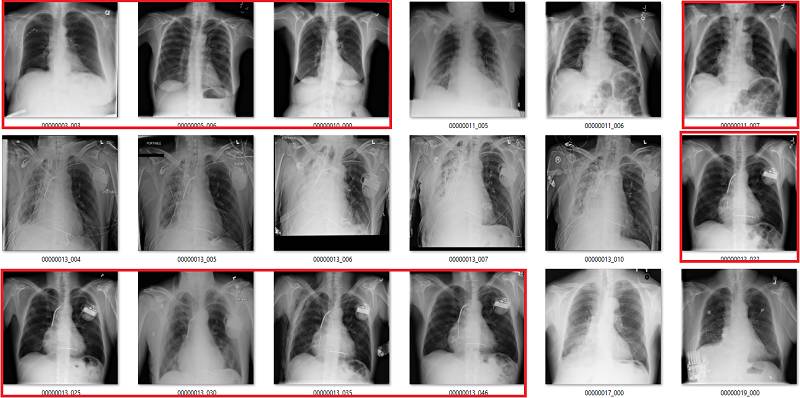

这部分要说该数据集中基于标签的图像。它们是随机选取包含 18 张图像的序列集,并非精挑细选。

我尽量保持谨慎,当一个案例模棱两可的时候,我选择标出标签类别。在所有图像中,红色 = 明显错误的标签;橙色 = 怀疑态度,我没有指出这个问题,但是不能排除这种怀疑。(出于临床诊断的习惯 :p)

肺不张(Atelectasis)

心脏扩大(Cardiomegaly)

纤维化(Fibrosis)

我的标签并不完美,其他放射科医生可能对其中的一些标签有疑惑。但是必须明确一点,我的标签和论文/附录中的结果有极大的不同。

我通常喜欢硬数据,因此我尽力量化标签准确率。事实上我发现其中的很多标签都很难定义,因此下表中未列出。我查看了每个类别中的 130 多张图像,根据我的视觉判断计算原始标签的准确率。这个数据量比较适合使用,因为 95% 的置信区间可能再扩大 5% 左右,所以我的误差率可能达到 20% 左右。

我的视觉分析 vs. 论文中的文本挖掘结果

我再次怀疑我的标签到底对不对,尤其是和一队胸部放射科医生的判断结果相比,但是如上表所示,差别也太大了。我认为上表中的数据证明这些标签无法匹配图像中显示的疾病。